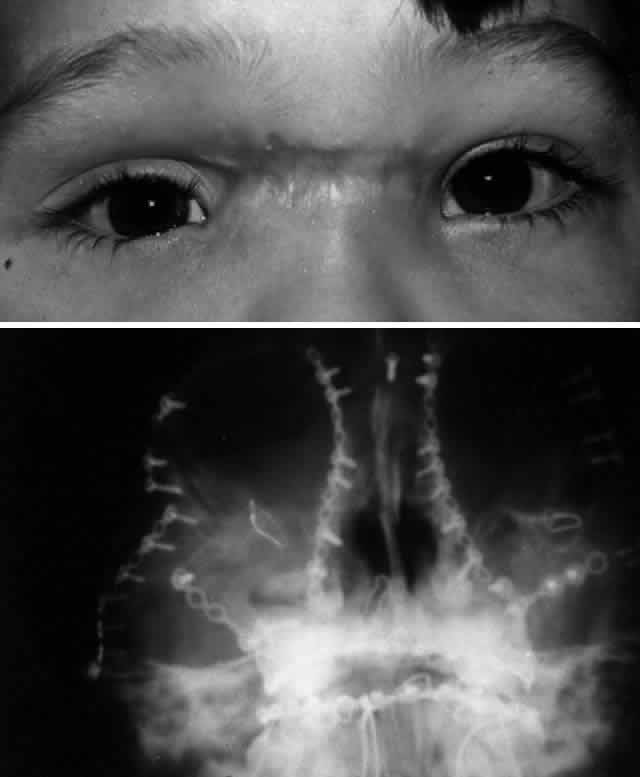

The position of the globe is also assessed (Fig. 3). As detailed previously, outward expansion of the orbital walls (blow-out fractures) can produce enophthalmos. Inward expansion of the orbital walls (blow-in fractures) can reduce orbital volume, potentially producing exophthalmos. In the early period after blunt orbital trauma, orbital edema and hemorrhage can transiently increase the orbital soft tissue volume, producing exophthalmos or “masking” the underlying potential for enophthalmos. As orbital edema subsides, the true globe position becomes evident. Over a more extended period of time (several months), soft tissue changes (cicatrization and, less commonly, fat atrophy) may contribute to the production of late enophthalmos. Globe position can be grossly assessed by direct visual inspection. Viewing the axial projection of the globes from above (“bird's-eye view”) or from below (“worm's-eye view”) facilitates a gross determination of axial globe position.

Fig. 3. A. Patient with blunt left orbital trauma demonstrates moderate enophthalmos of left eye (note deep superior sulcus). B. Slight restriction of supraduction in the left eye.

Quantitative exophthalmometry is performed for formal measurement of the degree of axial globe malposition. A difference of greater than 2 mm is considered abnormal. Typically a difference equal to or greater than 3 mm is required to produce an obvious clinical difference between the two eyes, although preexisting lid and facial morphology (e.g., prominent dermatochalasis or eyebrows) may make the difference clinically less obvious and minimize disfigurement. It is important to note that standard Hertel exophthalmometry may not be accurate if the lateral orbital rim is disrupted. The globe may also be displaced in a nonaxial direction, generally toward the area of least resistance. Hypo-ophthalmos (i.e., downward displacement of the globe) associated with disruption of the orbital floor is the most common nonaxial type of displacement. Globe dystopia can be assessed by the relationship of the globe to the surrounding anatomic landmarks and the contralateral eye (if not involved by the injury). Typically with hypo-ophthalmos, the globe sinks downward and the inferior corneal limbus may drop below the lower eyelid margin, producing a “setting sun” appearance. Globe dystopia can be measured with a ruler, noting the distance and direction of globe displacement in millimeters. In extreme cases of orbital floor disruption, the globe may actually subluxate into the maxillary sinus.33